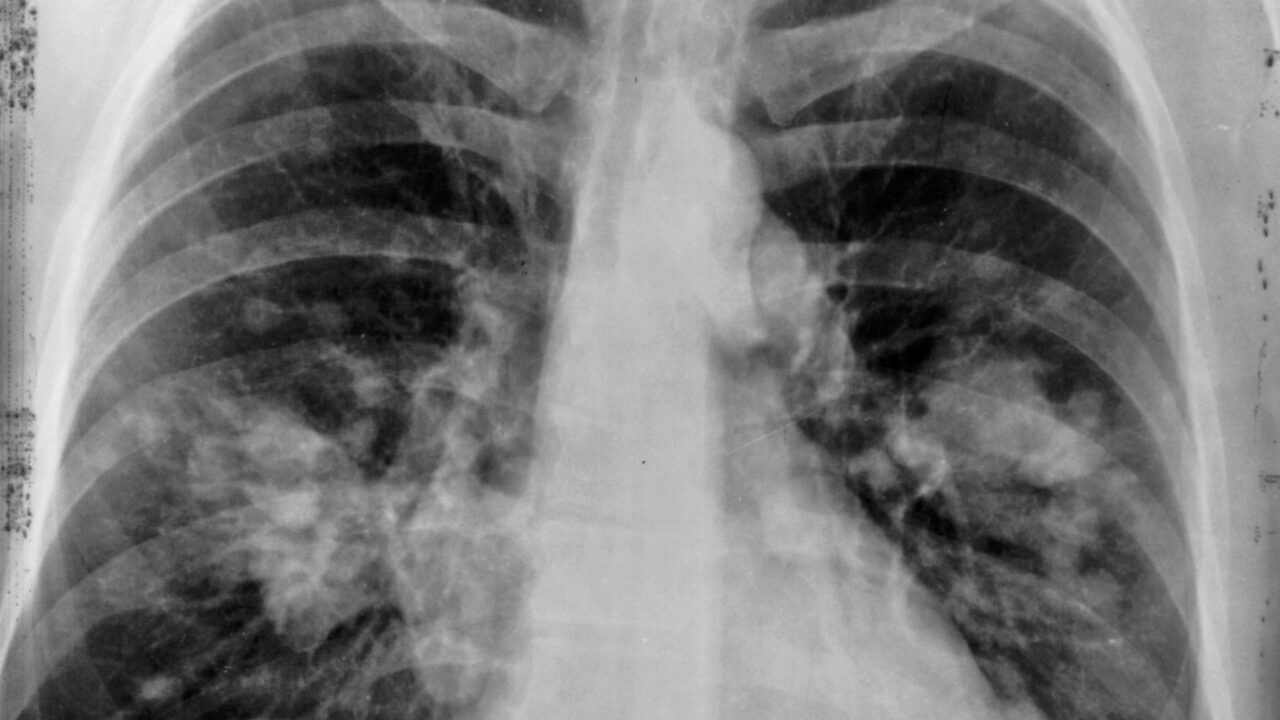

W leczeniu wczesnego raka płuca operacja wciąż pozostaje jedną z najważniejszych metod, bo daje szansę na całkowite usunięcie guza. Problem w tym, że wielu starszych pacjentów odpada już na etapie kwalifikacji – nie dlatego, że ich stan zdrowia to wyklucza, lecz dlatego, że przekroczyli 80. rok życia. Badanie przeprowadzone w Icahn School of Medicine at Mount Sinai i Mount Sinai Tisch Cancer Center podważa ten schemat

Naukowcy przeanalizowali 884 pacjentów z wczesnym niedrobnokomórkowym rakiem płuca, w tym 114 osób w wieku co najmniej 80 lat. Porównano wyniki leczenia chirurgicznego, przeżycie oraz jakość życia w obu grupach.

Badacze zwracają uwagę, że operacja ma największy sens wtedy, gdy nowotwór zostaje wykryty wcześnie. To właśnie wtedy szansa na skuteczne leczenie jest najwyższa.